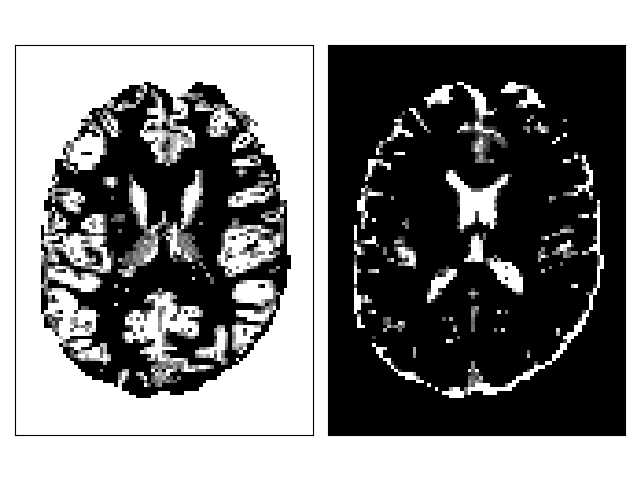

ACT Stopping Criterion#

Anatomically-constrained tractography (ACT) [2] uses information from anatomical images to determine when the tractography stops. The include_map defines when the streamline reached a ‘valid’ stopping region (e.g. gray matter partial volume estimation (PVE) map) and the exclude_map defines when the streamline reached an ‘invalid’ stopping region (e.g. corticospinal fluid PVE map). The background of the anatomical image should be added to the include_map to keep streamlines exiting the brain (e.g. through the brain stem). The ACT stopping criterion uses a trilinear interpolation at the tracking position.

include_map = pve_gm_data

exclude_map = pve_csf_data

act_criterion = ActStoppingCriterion(include_map, exclude_map)

fig.savefig("act_maps.png")

tracking stopping criterion

Include (left) and exclude (right) maps for ACT.